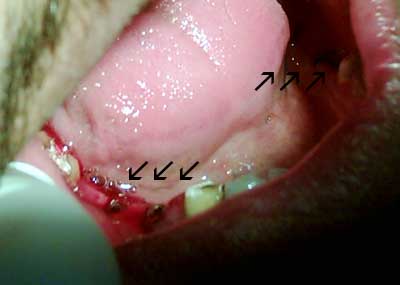

في اليوم التالي تمت زراعة 7 زرعات سويسرية خلال ساعتين وأنا لم أشعر بأي ألم خلال الزراعة لأنه بالواقع أسهل كثير من الذي كنت أتوقعه ، هو فقط خدر اللثة وزرع .